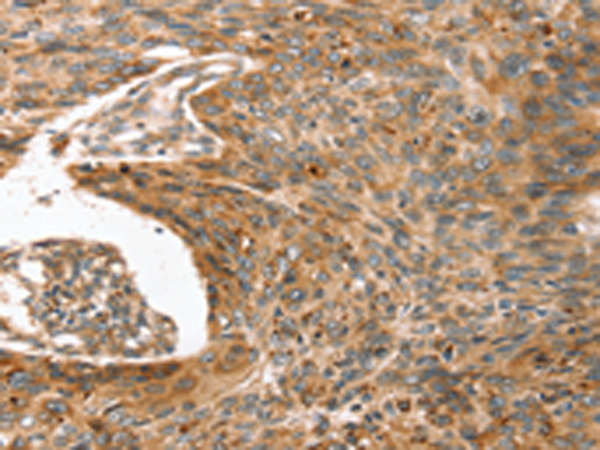

IHC positive control: |

Human esophagus cancer |

IHC Recommend dilution: |

25-100 |